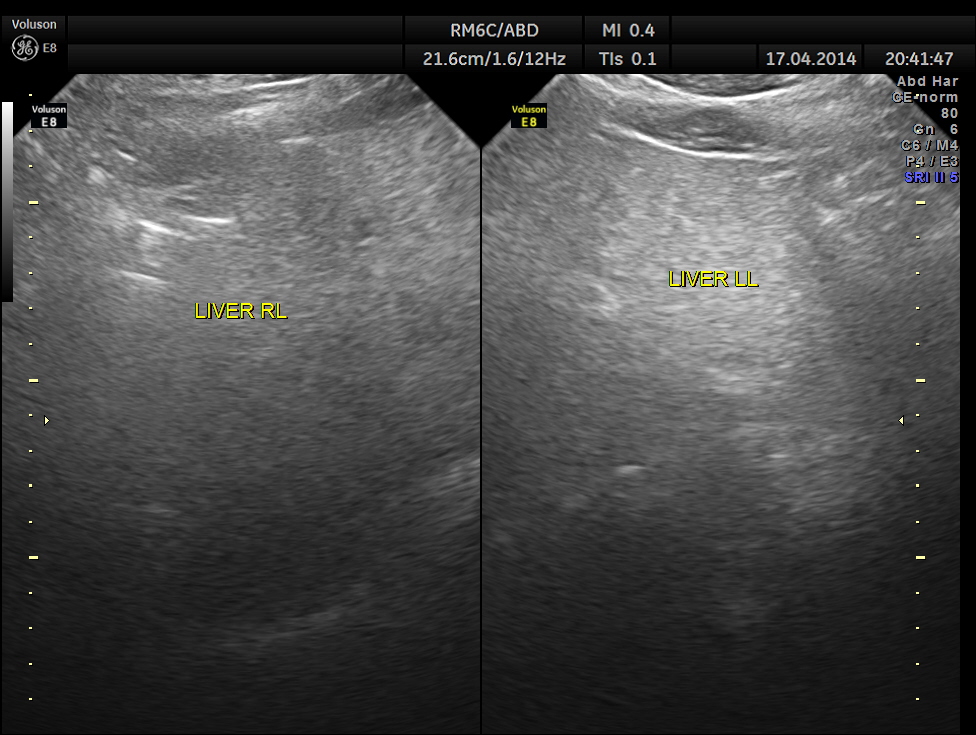

Two distinct mass lesions were seen in the right side of the abdomen in the lumbar and hypochondriac regions . Though they appeared distinct from the liver , it was a bit confusing.

The ultrasound gave us a few inconclusive findings . Uterus was massively enlarged ; a large fibroid was seen ; adenomyosis was seen ; endometrium was thickened ; two large mass lesions were seen in the right upper quadrant and right lumbar region . But it was difficult to ascertain the origin of these extra uterine masses .